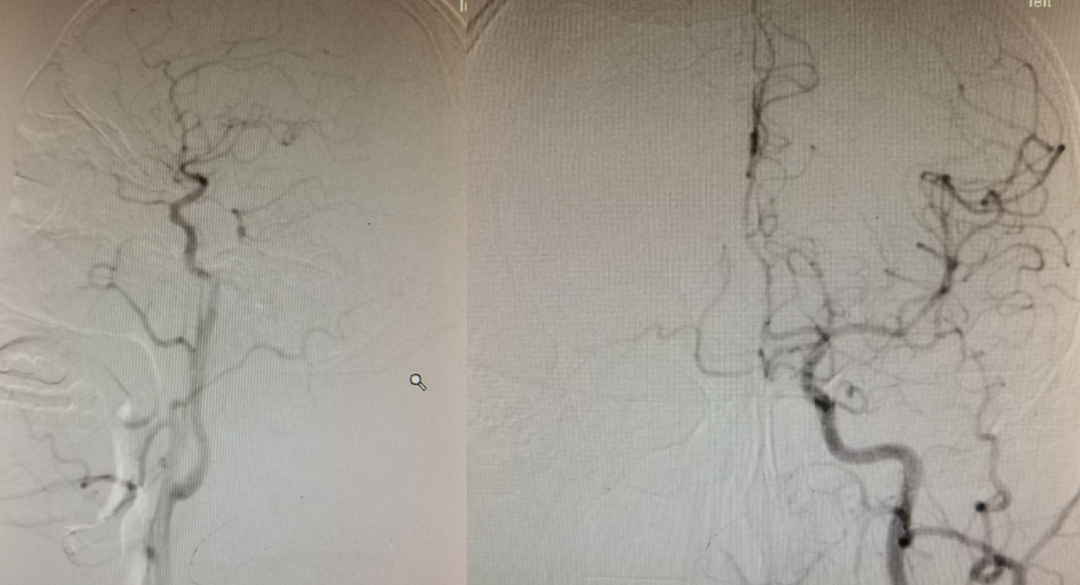

选择Neuroform EZ 3.5X20mm支架植入,术后工作角度造影如下:

术后标准正侧位。